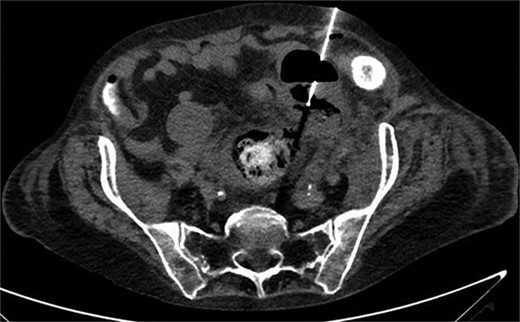

One month prior, the patient was admitted for complicated perforated sigmoid diverticulitis. Treatment included piperacillin-tazobactam (Zosyn), bowel rest, and fluid resuscitation. On hospital Day 6, her condition worsened with increased nausea, vomiting, and an elevated WBC count of 15. CT imaging revealed a 4.8 × 4.4 × 4.0 cm diverticular abscess, leading to CT-guided percutaneous drainage by interventional radiology (Figs 4–7). Cultures grew Citrobacter sedlakii and Enterococcus faecium vancomycin resistant Enteroccus (VRE), and treatment was adjusted to include Bactrim, followed by daptomycin and levofloxacin. The abscess resolved after 3 weeks, and the drain was removed before discharge. The patient was instructed to follow up with her surgeon and undergo a 6-week interval colonoscopy.

CT showing resolution of abscess with IR pigtail drain in place.